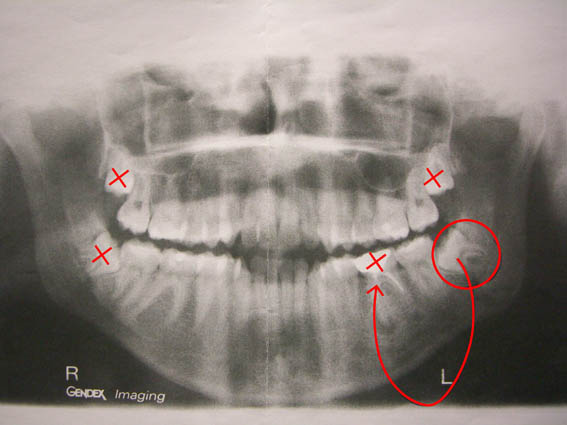

Τέλος οι γνωστοί σε όλους μας φρονιμίτες που δημιουργούν πολλά και έντονα προβλήματα, κυρίως σε νεαρή ηλικία και όχι μόνο.

Μία συχνή επέμβαση που πολλοί τη θεωρούν σχετικά απλή, αλλά στην πραγματικότητα πολλές φορές δεν είναι έτσι.

Σημαντικό είναι επίσης, κυρίως σε νέους η μεταμόσχευση δοντιών, όπου ανάλογα με την διάπλαση των ακροριζίων η επιτυχία της μεταμόσχευσης φθάνει σε μεγάλο ποσοστό. Έτσι το κενό που δημιουργείται μετά από απώλεια ενός μόνο γομφίου, μπορεί με μεγάλη πιθανότητα να κλείσει με μεταμόσχευση ενός φρονιμίτη στη θέση αυτή.